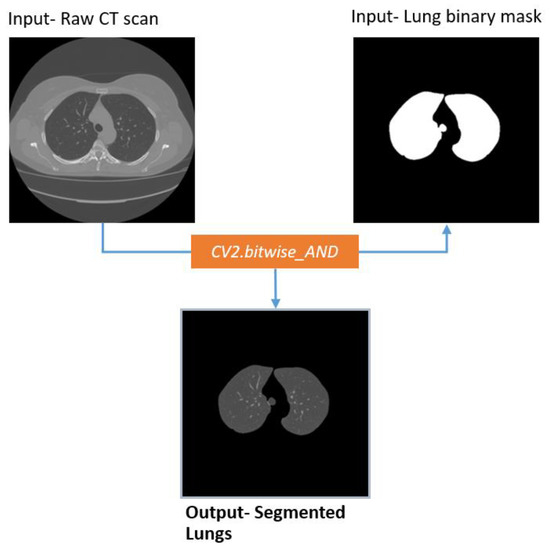

Extracting Lung

The segmented binary mask is fused with the source image employing a bitwise_AND operation (Figure 17). Thus, the lungs are segmented without losing any details.

Figure 17. Extracted lungs from Raw CT scan using lung binary mask.

Figure 17 illustrates that, after merging the binary mask with the raw CT image, the output contains only the lungs.